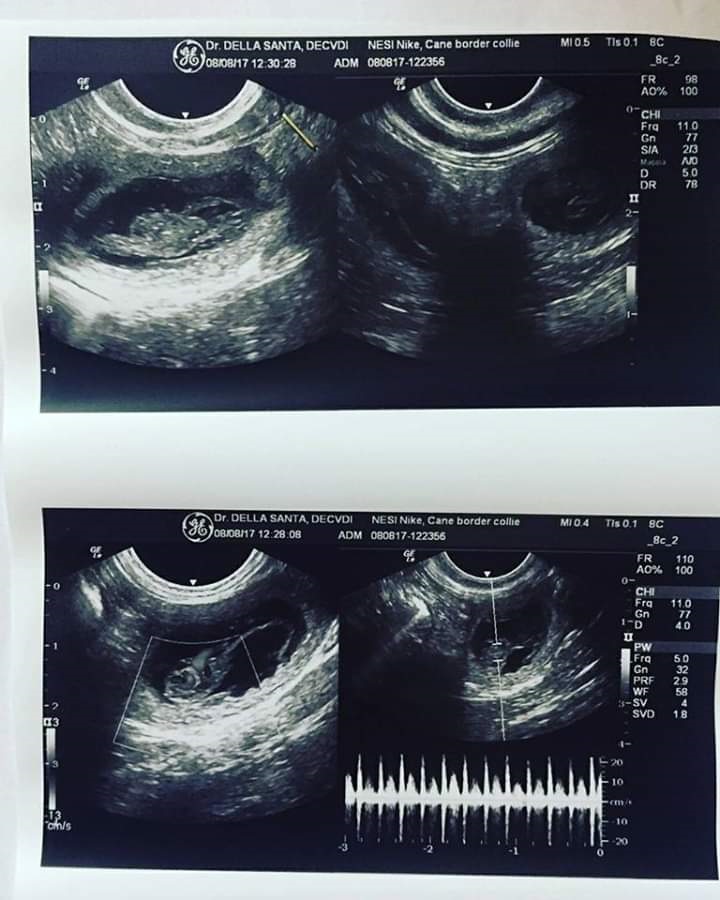

Se doveste in futuro decidere di far riprodurre la vostra cagnolina, resto a disposizione per aiutarvi e consigliarvi il maschio più adatto e fornirvi tutte le informazioni necessarie. Ricordatevi che è importante riprodurre solo individui che abbiano effettuato lastre ufficiali e test genetici.